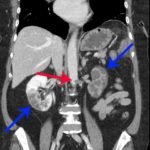

On the coronal sections of computed tomography (CT), bilateral renal infarctions (blue arrows) and several splenic infarctions (green arrows) are noted. Of particular interest, part of the clot totally occluding the left renal artery visibly extends into the aorta (red arrow). The vascular reconstruction image is remarkable for the absent left kidney, the unusual contour of the right kidney and the abnormal splenic blush.

Classic emergency medicine teaching dictates that when a patient with atrial fibrillation has abdominal pain “out of proportion” to the examination, one must consider mesenteric ischemia. Although the bowels clearly carry the highest embolic risk for abdominal viscera, other organs are at risk as well. This case illustrates a rare constellation of segmental splenic infarcts and bilateral renal infarction, with complete left renal artery occlusion stemming from multiple emboli.